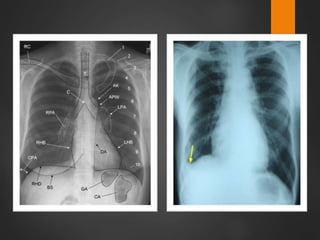

 El aire en el espacio pleural es

mas radiotransparente que el

pulmón.

 Con un neumotórax, la pleura

visceral se ve como una fina

línea blanca entre el aire del

pulmón y el aire en el espacio

pleural.

NEUMOTORAX